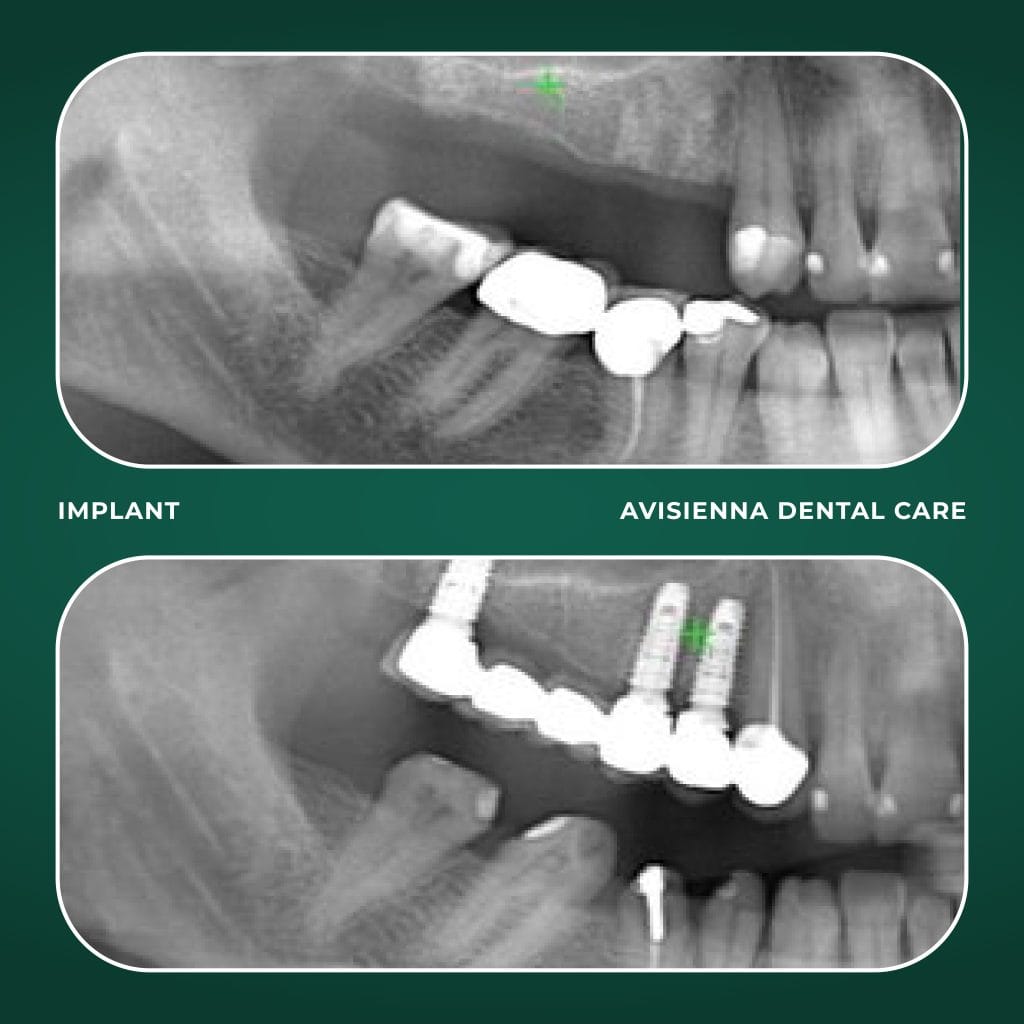

Dental implants are artificial tooth roots, typically made of titanium, that are surgically placed into the jawbone to support replacement teeth like crowns, bridges, or dentures. They serve as a long-term solution for missing teeth, mimicking the function of a natural tooth root.